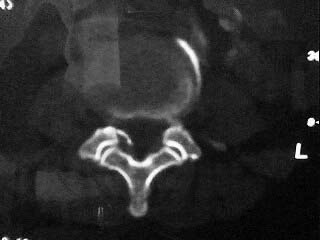

f,64。腰痛,腿麻三个月

是黄韧带钙化吗

腰椎退行性变;黄韧带钙化。

黄韧带增厚钙化

是!黄韧带钙化的诊断没问题!!